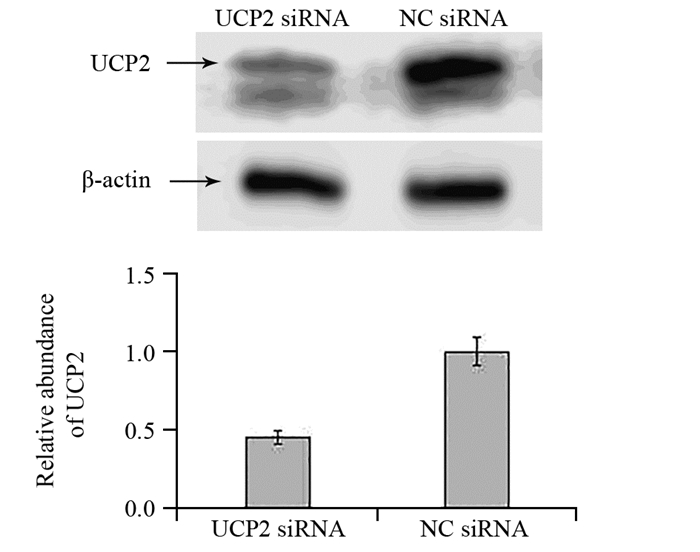

方法免疫组织化学法检测142例胃腺癌及25例癌旁正常胃黏膜组织中UCP2的表达情况,Pearson χ2检验分析其与临床病理特征的关系,Kaplan-Meier法及Cox风险回归模型分析UCP2的表达与胃腺癌患者预后生存的关系。将UCP2 siRNA转染SGC7901胃腺癌细胞系后,Western blot法检测UCP2蛋白的表达,EdU实验检测细胞增殖,划痕实验检测细胞迁移能力。

结果在胃腺癌组织中UCP2蛋白的阳性表达率明显高于癌旁正常胃黏膜组织(P=0.006),UCP2蛋白的表达与肿瘤浸润深度(P=0.024)、TNM分期(P=0.002)、淋巴结转移(P=0.001)显著相关;UCP2阳性患者5年生存率明显低于阴性患者(P=0.001)。在胃腺癌SGC7901细胞系中,UCP2高表达,沉默UCP2的表达能显著抑制肿瘤细胞的增殖,同时降低其迁移能力。

MethodsTotally 142 cases of gastric cancer and randomized 25 cases of normal gastric mucosa tissues in Tianjin Medical University Cancer Institute and Hospital were included. We used immunohistochemical staining to detect the expression of UCP2 and analyze its relationship with clinical pathological features. Kaplan-Meier method and Cox regression analysis were used to explore the correlation between the expression of UCP2 and the survival of gastric cancer patients. Western blot was used to detect UCP2 protein level after UCP2 siRNA transfection into SGC7901 gastric cancer cell lines. EdU assays and scratch assay were used to detect the proliferation and migration abilities.

ResultsThe expression of UCP2 in gastric adenocarcinoma tissues was significantly higher than that in adjacent normal tissues (65.5% vs. 28%, P=0.006). The expression of UCP2 in gastric adenocarcinoma tissues was significantly correlated with tumor infiltration (P=0.024), TNM stage (P=0.002) and lymph node metastasis (P=0.001). The 5-year overall survival of patients with positive UCP2 expression was significantly lower than those without UCP2 expression (P=0.001). Silencing UCP2 expression could significantly inhibit the proliferation and migration abilities of SGC7901 cell lines.